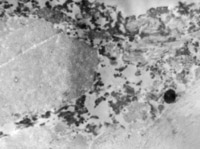

5-2-5 傷后第5天,膠原纖維相互融合,其間的細(xì)胞已崩解  TEM×6000